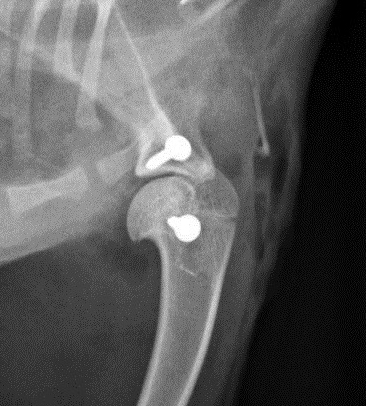

Die Röntgenuntersuchung beim Fachtierarzt für Chirurgie in Weiterstadt ergab, dass bei Ariel eine angeborene Missbildung vorliegt. Der rechte Oberarmknochen hat eine L-Form und zeigt nach hinten. Auch sind die Gelenkflächen nicht normal ausgebildet. Das führt dazu, dass Ariel die rechte Schulter nicht strecken und dadurch nur ganz gebückt laufen kann. Durch diese permanente Fehlhaltung ist leider auch das linke Schultergelenk luxiert (der Oberam luxiert nach außen und vorne). Ariel hat eine ganz schiefe Rückenlinie und die Prognose wäre nicht gut, wenn man nichts tut.....

Ariels deformierter rechter Oberarmknochen, der eine L-Form hat und nach hinten zeigt: